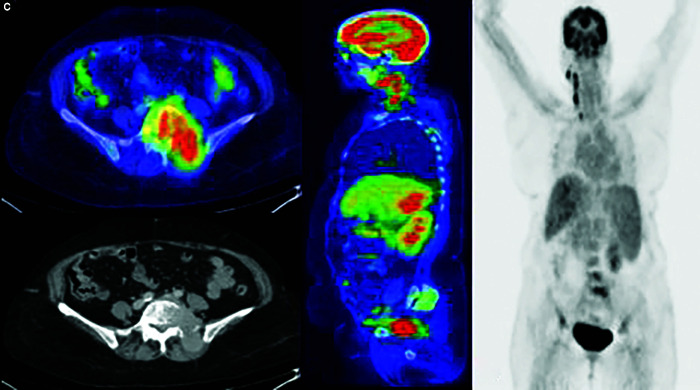

Results: Among the cohort of 51 patients, primary HCC was detected on FDG PET-CT in 43 individuals representing true-positive cases. Conversely, FDG PET-CT was unable to detect HCC in 8 cases, representing false-negative. Out of 51 patients, 74.5% of HCC cases exhibited multifocal pattern. The maximum standardized uptake value (SUV max) of the primary malignant site ranged from 1.9 to 16.1, with a mean of 3.7 ± 2.8. The FDG PET-CT revealed abnormal sites of the uptake outside liver in 23 individuals. The research confirmed the tumor recurrence in four previously treated patients. In the conducted investigation, FDG PET-CT showed 84.3% sensitivity for the diagnosis of HCC.